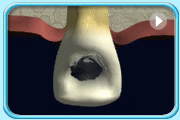

动画所见是清除部分牙髓的牙髓治疗过程。

动画所见是清除全部牙髓的牙髓治疗过程。